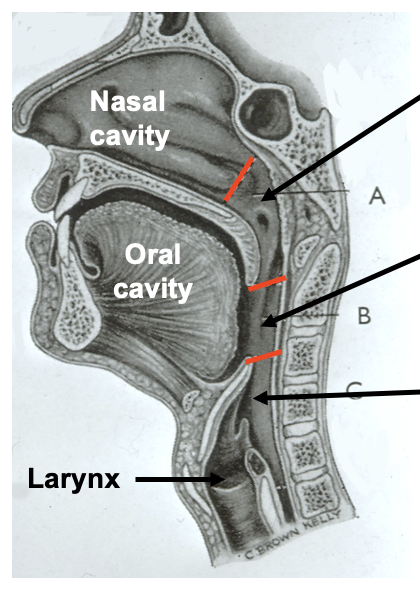

what are the divisions of the pharynx

regions of the pharynx

nasopharynx

oropharynx

laryngopharynx

oropharynx: which vertebrae is it level with posteriorly

body of the second cervical vertebrae

upper part of the third cervical vertebrae

laryngopharynx: borders

laryngopharynx

from the tip of the epiglottis

to the lower border of the cricoid cartilage

laryngopharynx: at which vertebrae is the cricoid cartilage level with

the cricoid cartilage lies at the level of C6

laryngopharynx: at which vertebrae is it level with posteriorly

the laryngopharynx extends posteriorly from the third to the sixth cervical vertebrae